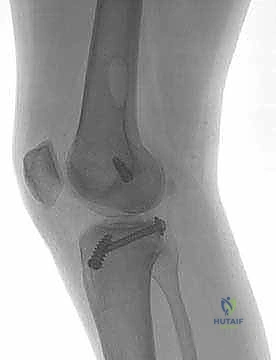

- الأشعة السينية (X-rays): لاستبعاد وجود كسور عظمية، خاصة كسور الانقلاع (Avulsion fractures) حيث ينفصل الرباط حاملاً معه قطعة من العظم.

- الأشعة السينية مع الضغط (Stress Radiographs): يستخدمها الدكتور هطيف أحياناً لقياس مقدار الإزاحة الخلفية بالملليمترات بدقة متناهية، مما يساعد في اتخاذ قرار الجراحة.

5. الكسور الانقلاعية (Avulsion Fractures): حيث يحتاج العظم المنفصل إلى تثبيت فوري بالمسامير.